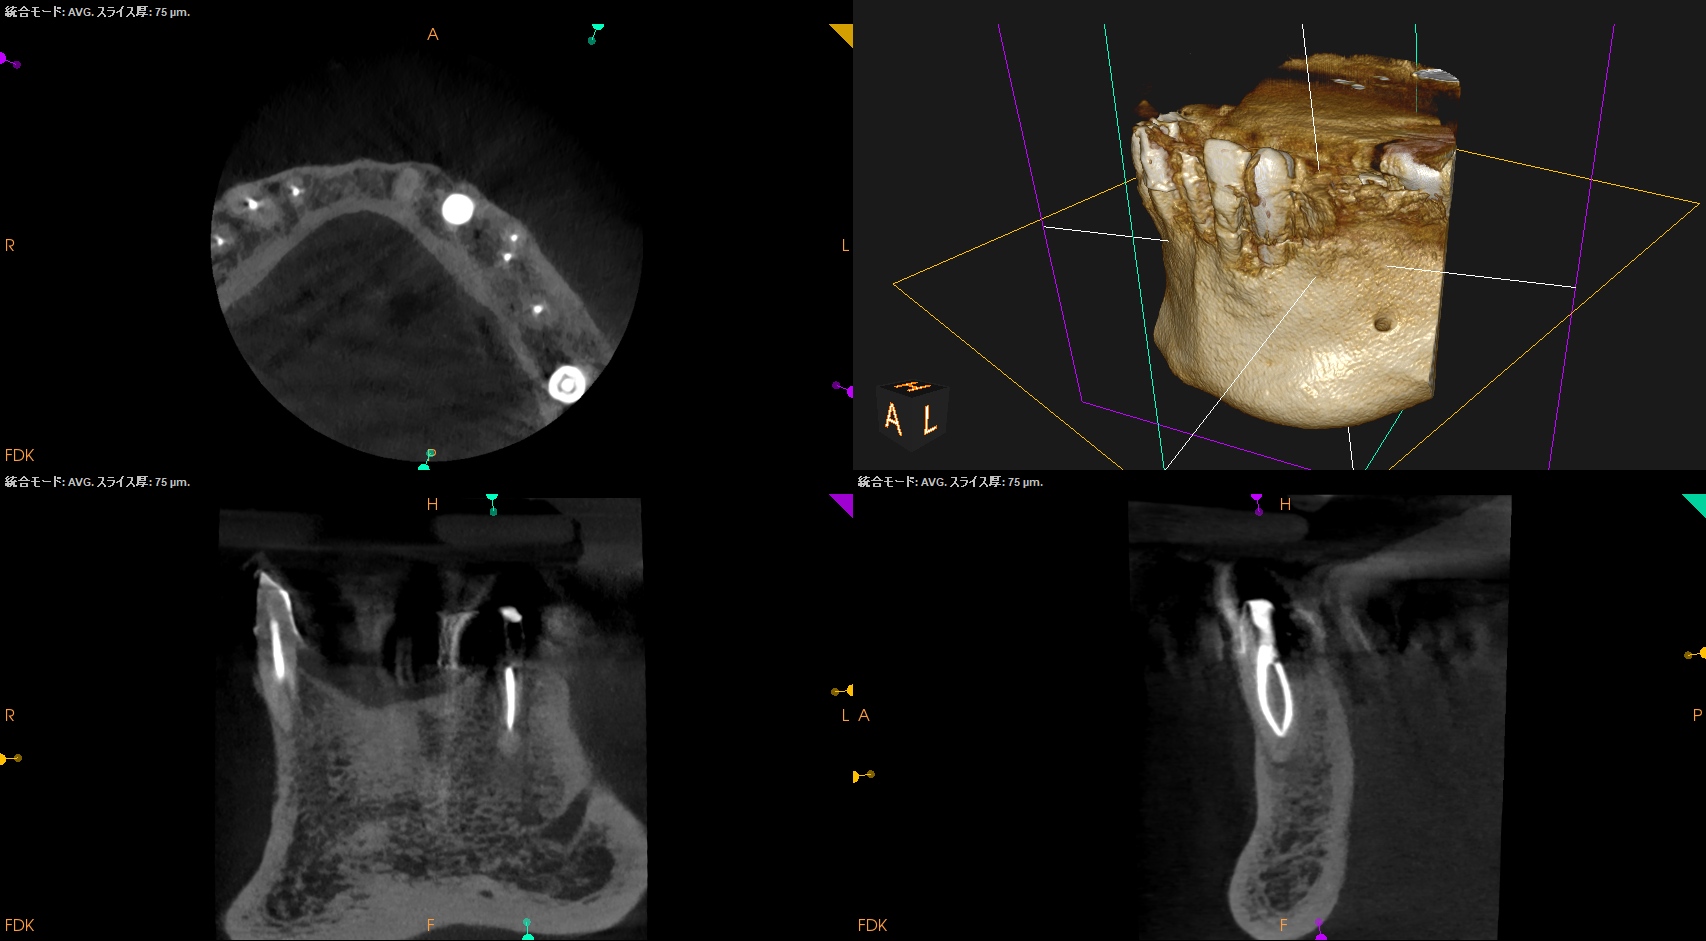

#21 Re-RCT 5M recall(2025.9.11)

穿通しなかったのに根尖病変は5ヶ月でほぼ消失した。

この現象に寄与したものはやはり、術前のコロナルリーケージだろう。そして再治療がそれを後押しした。そう。両方とも治療のKeyなのである。